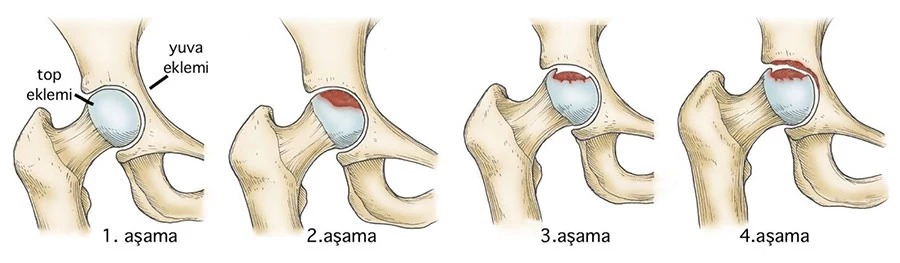

Ficat ve Arlet Sınıflandırması:

Evre 0: Röntgen ve MR normal. Semptom yok / Şüphe. (LR+ = 1.0)

Evre I: Röntgen normal, MR pozitif (Çift Çizgi). Hafif ağrı. (LR+ 15.0 - Tanı kesin)

Evre II: Skleroz, kistik değişiklikler. Belirgin ağrı. (LR+ 10.0 - Röntgen tanısaldır)

Evre III: Crescent Sign (Hilal Belirtisi). Şiddetli ağrı, subkondral kırık ve çökme başlar. (LR+ - ∞ - Biyomekanik iflas)

Evre IV: Eklem aralığında daralma, ileri osteoartrit. Terminal safha.